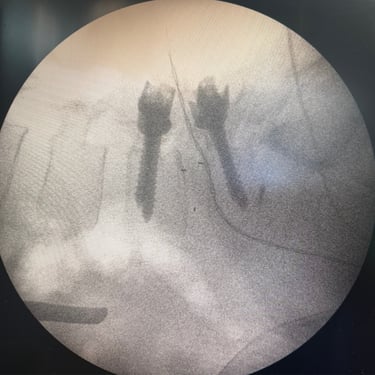

Listesis Lumbar: Artrodesis con Tornillos Transpediculares y Fusión Intersomática Transforaminal (TLIF).

La listesis lumbar es el deslizamiento anormal de una vértebra sobre otra, lo que puede generar dolor lumbar crónico, inestabilidad y compresión de las raíces nerviosas. Cuando el tratamiento conservador no es suficiente, la artrodesis con tornillos transpediculares (FTP) asociada a la fusión intersomática transforaminal (TLIF) es una técnica quirúrgica efectiva. Este procedimiento permite estabilizar la columna, restaurar la alineación vertebral y lograr una fusión sólida, al mismo tiempo que descomprime las estructuras nerviosas. La combinación de estas técnicas mejora el control del dolor, la función neurológica y la calidad de vida del paciente.